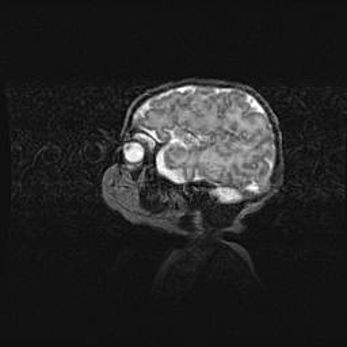

Наружная гидроцефалия с возможной атрофией височных областей.

Возраст: 28 дней

Вес: 3670 г

Пол: мужской

Окружность головы: 38 см

Срок гестации: 40 недель

Гидроцефалия головного мозга у новорожденных – это заболевание, которое характеризуется скоплением избыточного количества спинномозговой жидкости в желудочковой системе головного мозга в результате затруднения её перемещения от места выработки к месту поглощения в кровеносную систему или вследствие нарушения абсорбции. При открытой наружной форме гидроцефалии у новорожденных расширяются и переполняются субарахноидные пространства.

При нормотензивных  формах,  которые,  как  правило,  являются  следствием  перенесенных ишемических  повреждений  паренхимы  мозга,  возможно  сочетание микроцефалии  с нормотензивной гидроцефалией. В основе данных изменений лежит атрофия больших полушарий с преимущественной  локализацией  в  лобно-височных  областях.